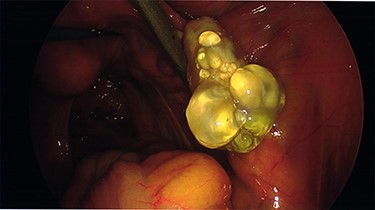

Intraoperative findings were inconsistent with all pre-operative ultrasound diagnoses. Both ovaries appeared suspicious for malignancy with cystic lesions covering the surface of the right, while the left appeared to contain two smaller cysts (Figs 3–5). There were no hydrosaplinges or free fluid within the pelvis. Given the abnormal features of the ovaries, the surgeon proceeded with the laparoscopic BSO without spillage. Pelvic washings were performed, though there were no atypical peritoneal or omental lesions for biopsy.

The intra-operative photos demonstrating multiple cystic structures covering the surface of the right ovary.